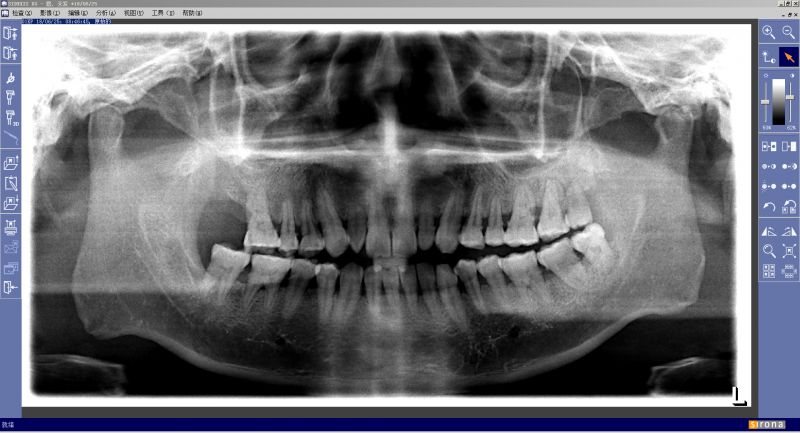

张先生的种牙前牙片(左侧的缺牙一颗)